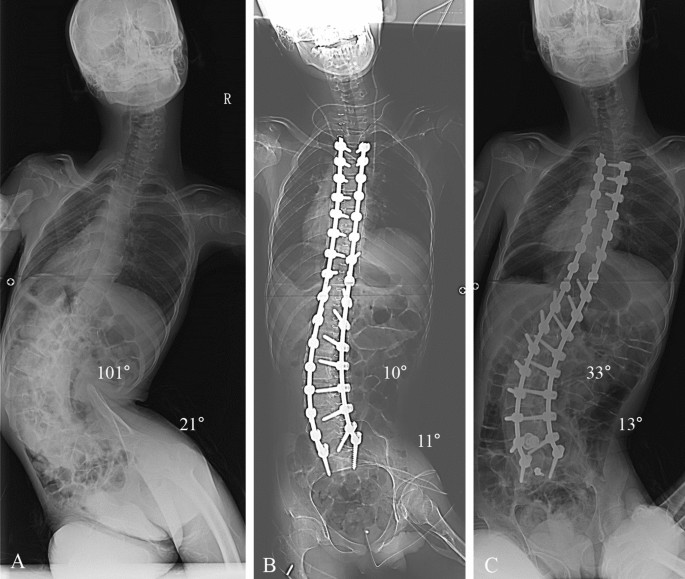

This study was designed as retrospective, comparative analysis at a single institute where deformity correction was routinely performed. All deformity correction procedures were performed by a senior spine surgeon with vast experience in performing standard open surgeries. Considering the effect of pelvic fixation on surgical outcomes, we enrolled patients with NMS who underwent deformity correction from 2009 to 2016. Patients with Cobb’s angle less than 40º and/or PO less than 15º were excluded in our study. A total of 77 patients was included and divided into three groups as follows: the pelvic fixation group (n = 16, NMS patients who underwent pelvic fixation) (Fig. 1), fixed to S1 group (n = 33, NMS patients who underwent fixation to S1 without pelvic fixation) (Fig. 2), and fixed to L5 group (n = 28, NMS patients who underwent fixation to L5 without pelvic fixation) (Fig. 3). This study was performed after obtaining approval of the institutional review board of Korea University of Guro Hospital. The present study was performed in accordance with the contemporary amendments of the Declaration of Helsinki and within an appropriate ethical framework. Both children and parent and/or legal guardians were informed of the purpose of the study, agreed to participating, and signed informed consent for both study participation and publication of identifying information/images in an online open-access publication.

Deformity correction from T3 to S1 in patients with neuromuscular scoliosis (NMS). (A) A 16-year-old male patient who diagnosed with cerebral palsy (spastic quadriplegia) showed neuromuscular scoliosis. The whole-spine anterior–posterior image showed 101° of scoliosis deformity, and pelvic obliquity was 21° as measured by pelvic tilting angle. (B) The immediate postoperative radiograph showed 10° of the Cobb’s angle (90.1% of correction rate) and 11° of the pelvic tilting angle (47.6% of correction rate, which are not performed by spinopelvic fixation). (C) The 2-year follow-up Cobb angle was 33° and pelvic obliquity was 13°.